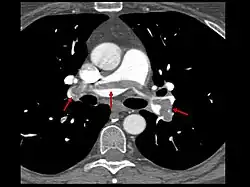

- Le scanner spiralé des artères pulmonaires[12] ou angioscanner des artères pulmonaires : un produit de contraste iodé est injecté en intraveineux. Le mouvement rotatif et longitudinal (caractère spiralé) de la tête du scanner permet de bien visualiser les artères pulmonaires proximales et moyennes et un peu moins bien leur distalité. C’est un excellent examen de diagnostic positif et de gravité, même si les risques liés à l’emploi de produits iodés et la radiation persistent. Il est moins invasif que l'angiographie conventionnelle. Il permet aussi l'évaluation de plusieurs autres structures intrathoraciques (aorte et médiastin, poumon, plèvre), en plus de l'évaluation des artères pulmonaires. Il est considéré souvent comme le nouvel examen de référence.